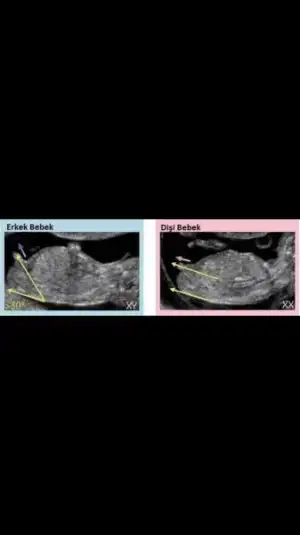

Öyle miydi kiparalel olunca erkek değil miydi ? ay grubu cinsiyet heyecanı sardı ne güzel

aygokbulutt banada kız gibi geldi nub teorisine göre bedenine paralel gibi alt fotoda

Evet kanama alanı olusmus. Cınsıyet kesın erkek.yatısa devam. Haftada bır ıgne devam progestan gunde 3 devamKanama alanı oluşmuş mu Orayı anlyamadum.cinsiyet kesin mi